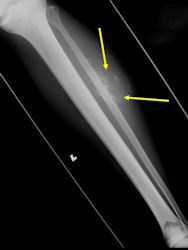

There are 3 radiographic presentations for osteosarcomas, depending upon the amount of osteoid/ossification and calcium deposition:

- Mixed sclerotic and lytic, permeative lesion most common radiographic presentation

- Purely osteoblastic, permeative lesion: dense sclerosis and osteoid production

- Purely lytic, permeative lesion: little osteoid production and/or minimal calcium deposition in osteoid

Conventional osteosarcomas are permeative lesions on plain radiographs (borders of the lesion cannot be clearly delineated)

- Wide zone of transition from lytic/sclerotic areas of tumor to normal bone

- Makes borders of lesion hard to define

- Most (90%) arise from the metaphysis of the bone

- Rarely (10%) arise from the diaphysis

- Most conventional osteosarcomas (90-95%) extend through the bone into the soft tissues and form a soft tissue mass outside of the bone